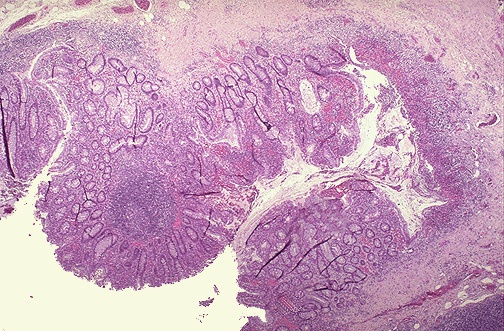

Microscopic examination shows diffuse mucosal ulceration, with several ulcers extending to the muscularis propria.